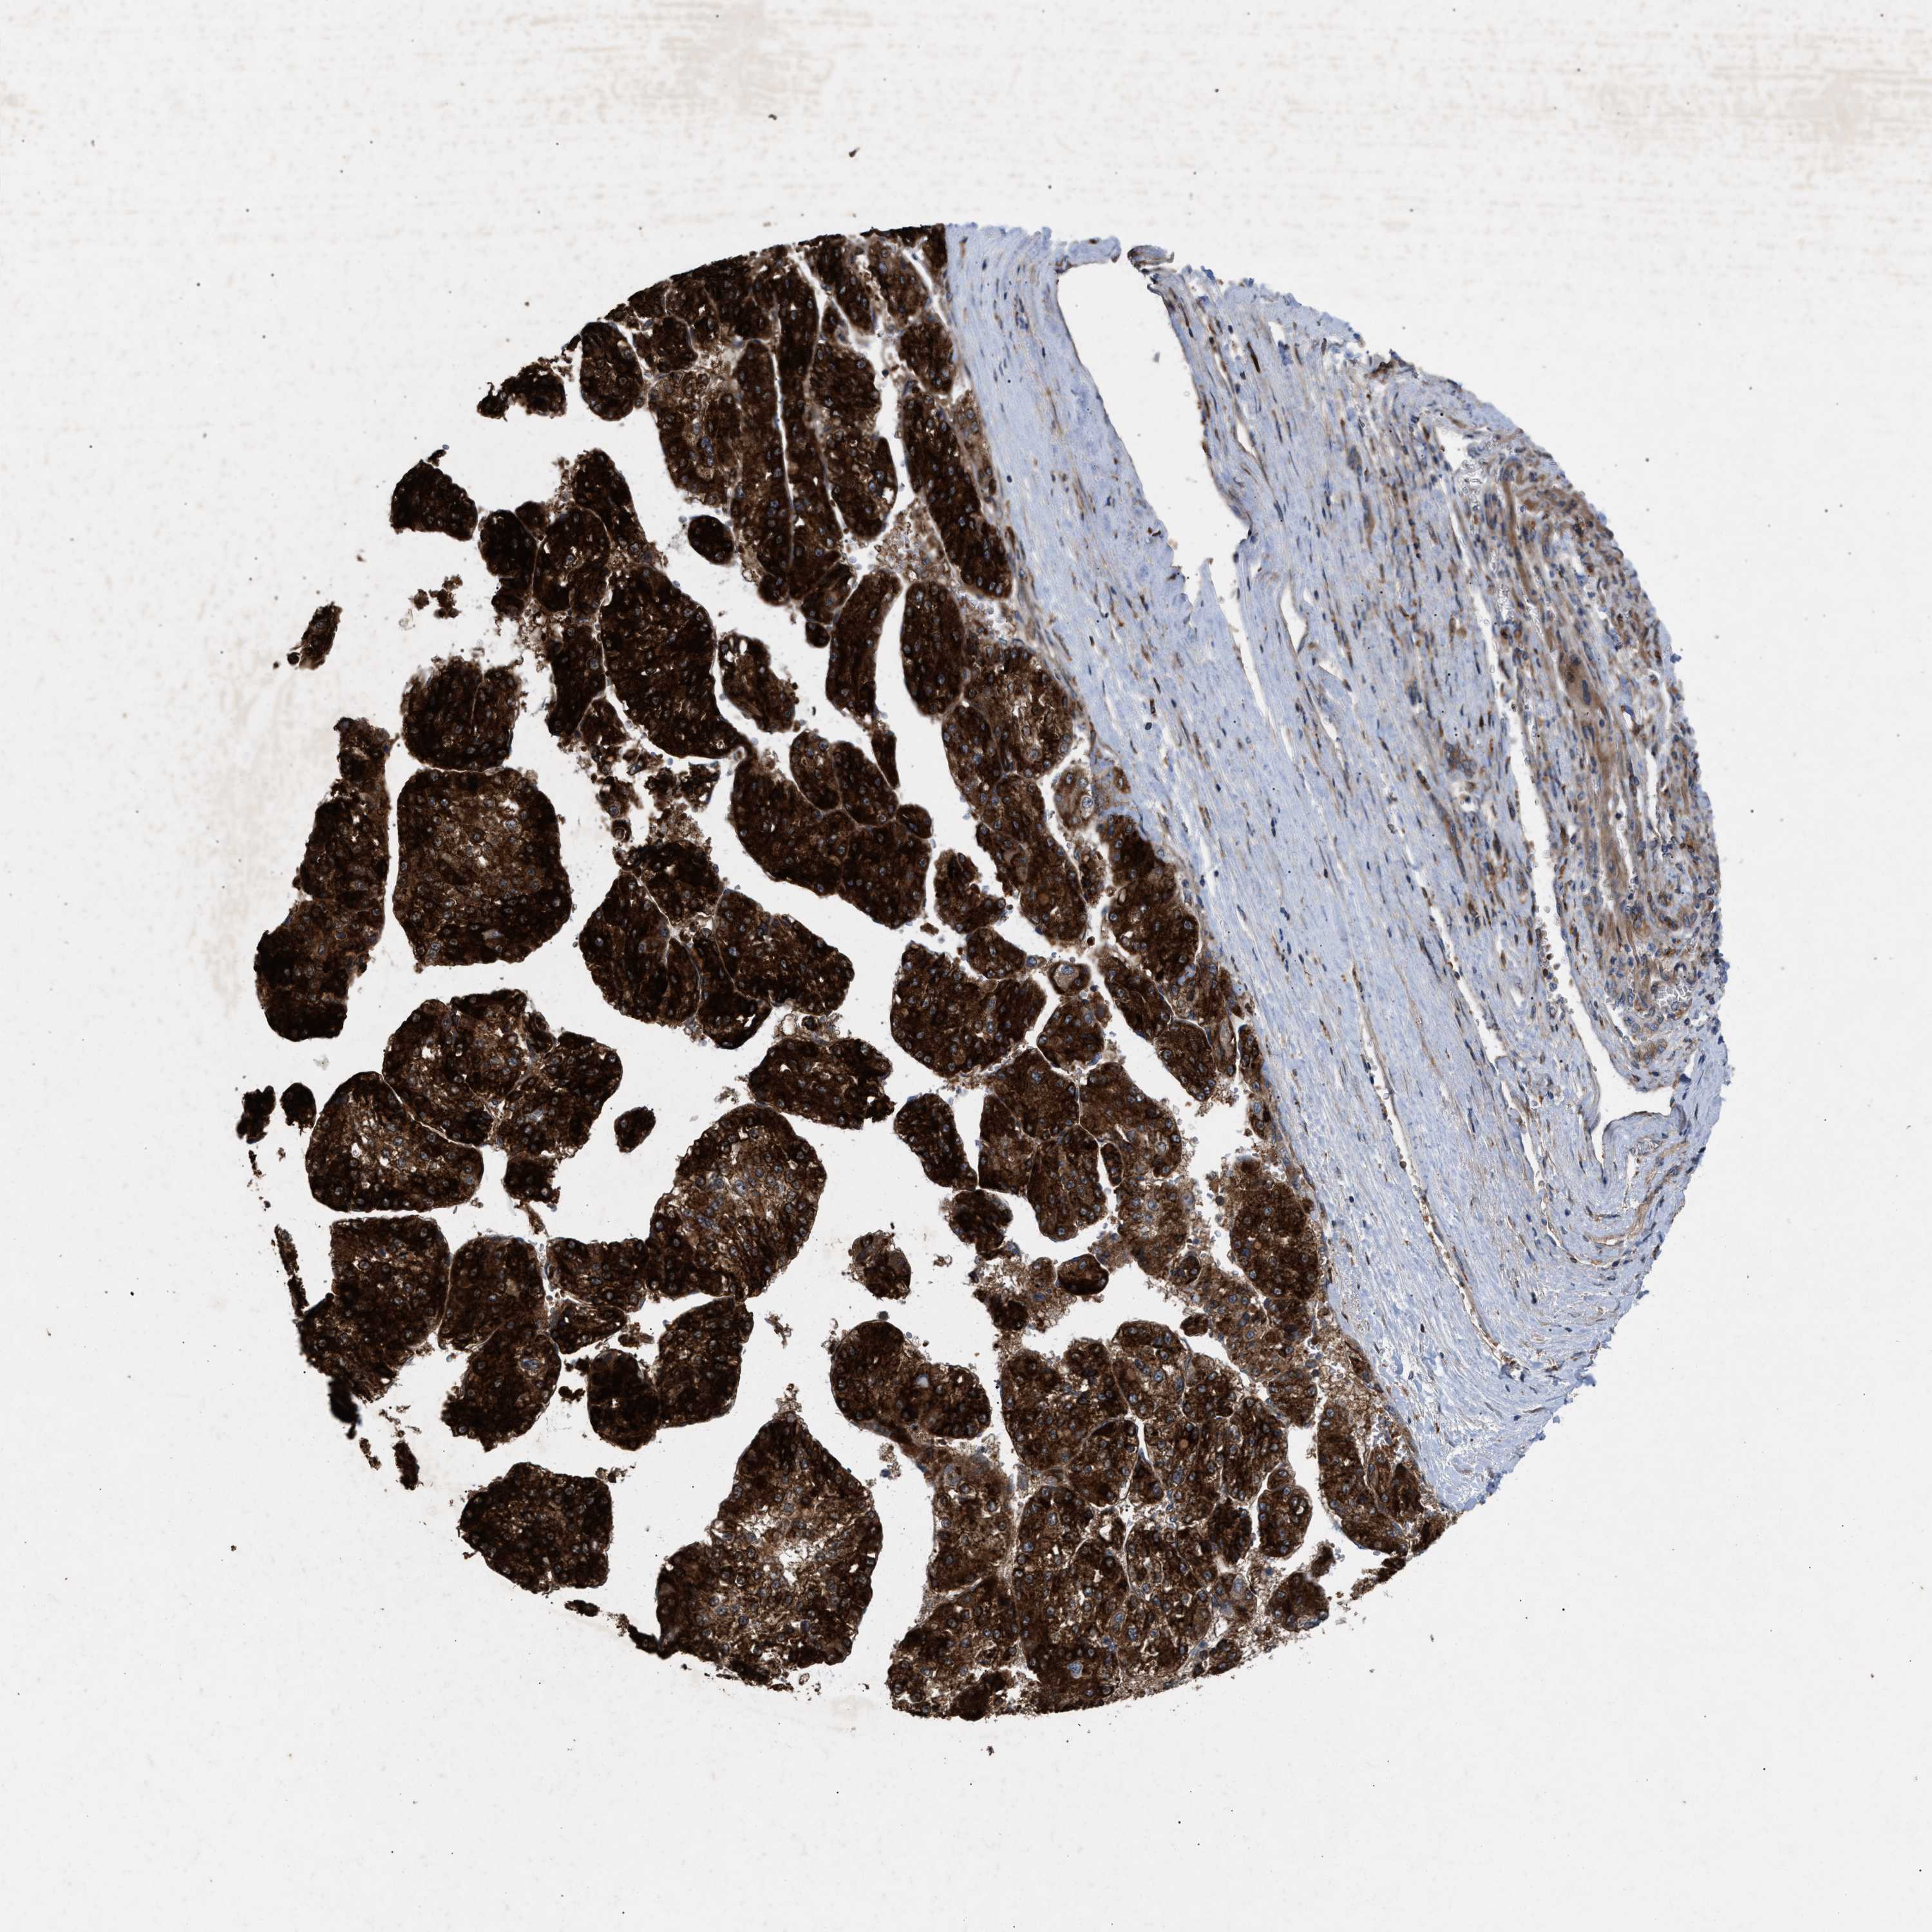

LIVER CANCER - Protein expressioni

A mouse-over function shows sample information and annotation data. Click on an image to view it in a full screen mode. Samples can be filtered based on level of antibody staining by selecting one or several of the following categories: high, medium, low and not detected. The assay and annotation is described here.

Note that samples used for immunohistochemistry by the Human Protein Atlas do not correspond to samples in the TCGA dataset.

Antibody stainingi

Antibody staining in the annotated cell types in the current human tissue is reported as not detected, low, medium, or high, based on conventional immunohistochemistry profiling in selected tissues. This score is based on the combination of the staining intensity and fraction of stained cells.

Each image is clickable and will lead to virtual microscopy that enables deeper exploration of all samples and also displays staining intensity scores, fraction scores and subcellular localization as well as patient and tissue information for each sample.

Antibody HPA019369

Antibody HPA021323

Staining

High

Medium

Low

Not detected

Intensity

Strong

Moderate

Weak

Negative

Quantity

>75%

75%-25%

<25%

None

Location

Nuclear

Cytoplasmic/membranous

Cytoplasmic/membranous,nuclear

Cholangiocarcinoma

Carcinoma, Hepatocellular, NOS